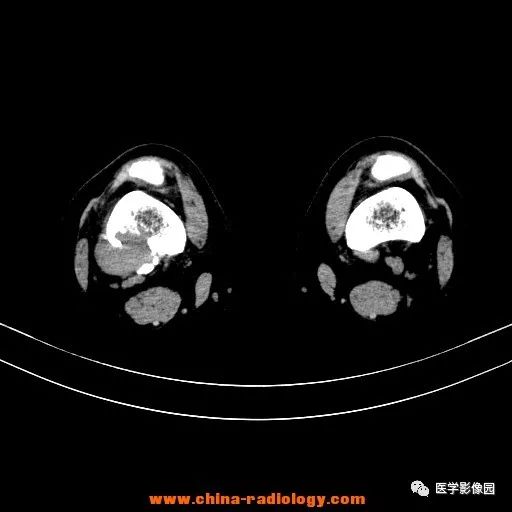

患者女性,29岁,右膝关节痛疼3月余,局部无红肿。

影像学表现:右股骨远端外后方可见局限性骨质破坏及软组织肿块,边界清楚。

病理结果:梭形细胞瘤